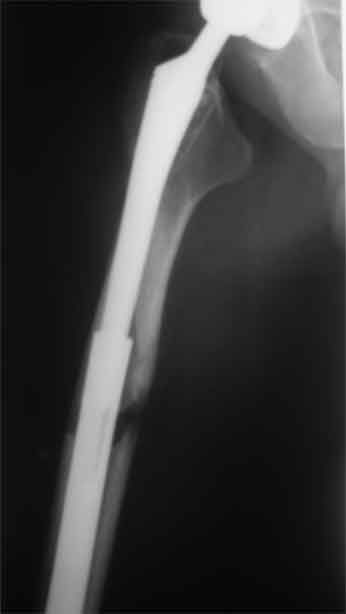

Произведено закрытое удлинение ножки эндопротеза с помощью ретроградного интрамедуллярного стержня. Продолжительность операции 3 часа. Два из них закрытое восстановление длины бедра диистрактором

таз-бедро.

новые снимки